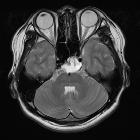

MRI

A stalk-like connection to the clivus is usually seen if high-resolution images are obtained.

Apart from the characteristic location (retroclival, prepontine, and intradural), MRI findings are non-specific, with signal similar to CSF:

- T1: hypointense

- T2: hyperintense

- T1 C+ (Gd): variable, however, most cases have not shown substantial enhancement